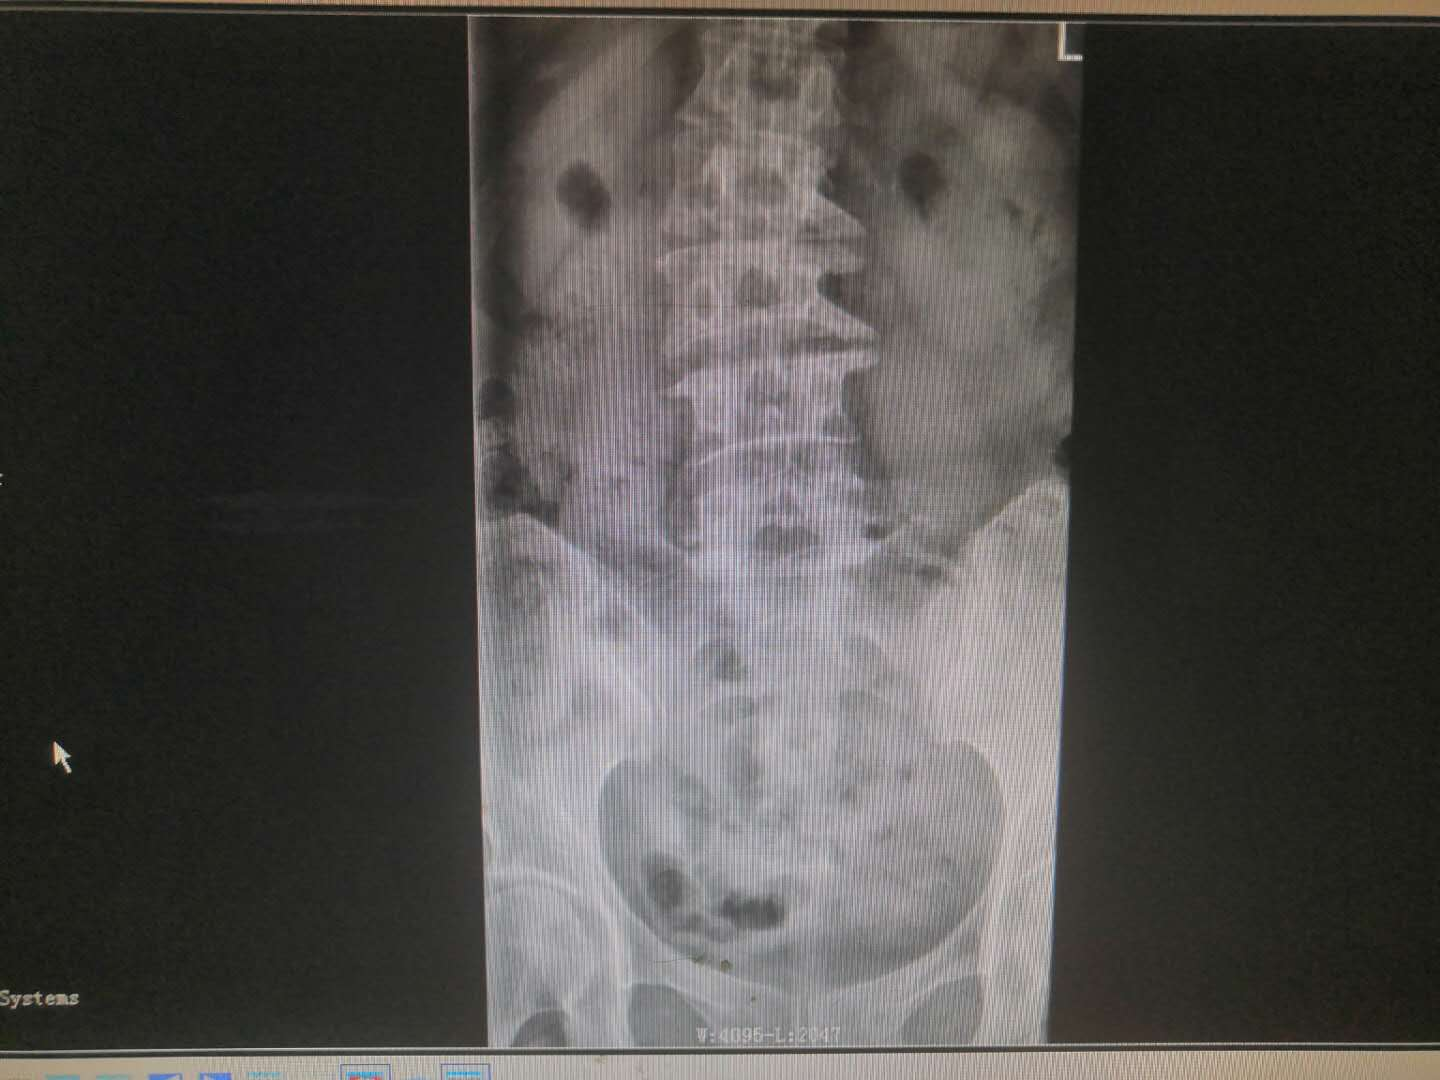

患   者:杨某,女,56岁。

主   诉:因反复腰痛伴右下肢疼痛麻木8年,加重6月,入院治疗。

现病史:缘于8年前开始无明显诱因出现腰部疼痛,呈间歇性胀痛,持续时间数分钟至数小时不等,放射至右下肢,伴右下肢麻木,此后症状反复出现,持续时间数小时至数天不等,劳累后加重,休息后缓解,6月前加重,并出现间歇性跛行,目前行走约200米左右需休息后方能继续行走,在当地医院治疗(药物+理疗)后效果欠佳,现特至我院就诊。

专科检查:颈胸椎各棘突无明显压痛,颈部活动正常,L3-5棘突及椎旁存轻压痛及叩击痛,疼痛无放射,腰部屈伸活动轻度受限,右下肢直腿抬高试验阳性(40度),加强试验阳性,双侧跟臀试验阴性,拾物实验阴性,右侧股四头肌、右足拇背伸肌力约4级,右小腿后、外侧、足背、足底感觉较左侧减退,肢端血运正常。

术前影像资料:

诊       断:

腰椎滑脱症(腰5向前III度)并腰椎管狭窄症。

治疗方案:

入院讨论后予在全麻下行腰4、5、骶1椎弓根螺钉内固定+腰5滑脱复位+腰5/骶1髓核摘除并Cage植入椎间植骨融合术。